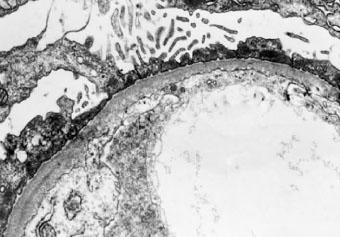

光镜下肾小球基本正常,免疫荧光检查一般无免疫沉积物,电镜下的弥漫性上皮足突消失或融合为其典型病变(图2—5)。有时也可见到局灶的系膜区有电子致密物。在微小病变性肾病病程发展到后期出现的局灶硬化性损害。微小病变性肾病有时在免疫荧光下也可见系膜区有IgM、IgA或C3沉积,一般很轻微。系膜细胞增殖和IgM沉积如同时出现,常提示对激素疗效差或对激素的反应延迟,并且使疾病进展的可能性增大。

图2—5 微小病变性肾病,上皮细胞足突融合(电镜 x8000)